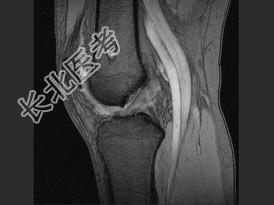

- 单项选择题女,21岁, 右膝部感不适,结合图像, 最可能的诊断是 ( )

A、股骨骨囊肿

B、股骨内生软骨瘤

C、股骨巨细胞瘤

D、股骨血管瘤

E、股骨结核